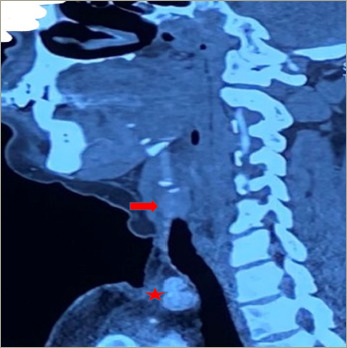

Parathyroid carcinoma is a rare endocrine neoplasm that accounts for <1% of cases of primary hyperparathyroidism. The management of parathyroid carcinoma is a challenge due to the high rate of local recurrence of the tumour. We report the case of a middle-aged north Indian woman who presented with recurrent primary hyperparathyroidism due to parathyroid carcinoma. She presented with a recurrent palpable hard neck mass and underwent radical dissection of the neck six times. At the time of writing this report, she was referred for external beam radiotherapy to the neck. Parathyroid carcinoma is a rare malignancy with an indolent but tenacious course. Complete resection at the time of initial surgery determines the prognosis of the neoplasm. Chemotherapy and radiotherapy are usually ineffective. Hypercalcaemia needs to be aggressively managed. A multidisciplinary team is required to effectively manage parathyroid carcinoma.